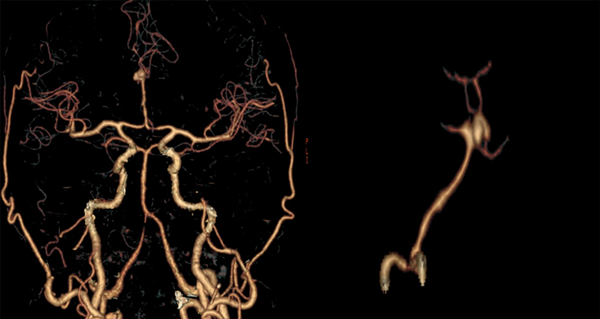

Paciente masculino de 47 años sin antecedentes patológicos de importancia, refiere inicio de enfermedad actual con cefalea súbita, severa, holocraneana, irradiada a región occipitocervical con vómitos en proyectil, desorientación, midriasis e incontinencia urinaria; es remitido a nuestra institución a los 16 días desde el inicio de los síntomas. Al ingreso se observa meningismo, trastornos en el nivel de conciencia e hipertensión arterial. En la tomografía de cerebro (TC) se observa una hemorragia subaracnoidea con un hematoma frontal bilateral. Se realiza angiotomografía cerebral donde se evidencia aneurisma sacular mediano trilobulado de ACAa (Figuras 1 y 2). Al examen físico de ingreso: bradipsíquico, bradilálico, somnoliento, desorientado, GCS 12/15 (respuesta ocular: 3, respuesta verbal: 3, respuesta motora: 6), pupilas isocóricas normorreactivas, sin focalidad de nervios craneales, vías largas: paraparesia 4/5 puntos (Daniels), rigidez de nuca leve y signo de Kernig. Se indica nimodipina 60 mg vía oral, medidas antiedema cerebral. Durante los días 2 y 24 de hospitalización se mantiene con clínica WFNS I, excepto el día 11 de hospitalización, donde se presenta deterioro neurológico por desorientación a WFNS II con evidencia de hiponatremia moderada (129 mEq/L). Se solicita tomografía cerebral simple control en la que se descarta resangrado e hidrocefalia, se indica corrección de sodio plasmático con mejoría evidente del estado neurológico a WFNS I. Se plantea intervención quirúrgica a las tres semanas del ingreso.

Figura 2. Angiotomografía cerebral. En reconstrucción 3D se evidencia circuito anterior: confluencia de ambos segmentos A1 (sin presencia de complejo comunicante anterior) en un tronco arterial único A2, presenta un aneurisma sacular trilobulado mediano en su bifurcación con domos que se disponen hacia arriba y hacia adelante. Cuello: 6.16 mm, alto: 6.39 mm y ancho: 8.17 mm.